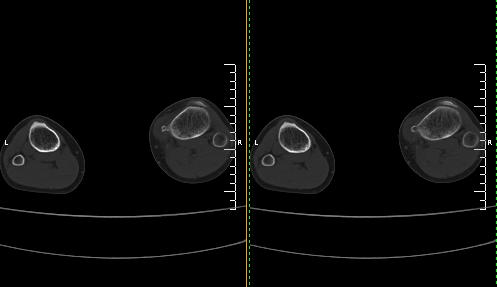

标题: CT19091:右胫骨近段骨性突出. [打印本页]

标题: CT19091:右胫骨近段骨性突出.

男,15岁,右胫骨近段软组织肿胀,下肢疼痛10左右.

右胫骨近端内侧骨性突起,皮质连续,骨质结构正常,首先考虑胫骨骨软骨瘤,随访观察。

右胫骨上端内侧骨软骨瘤可能性大。